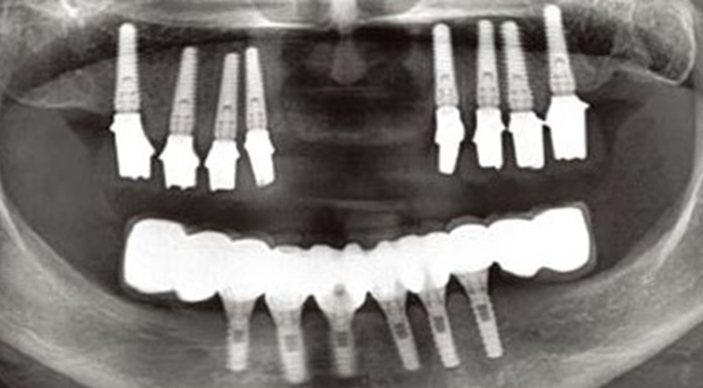

Clinical case: Full-mouth implants for mandibular & maxilla - restored using mixed prostheses

- Courtesy of Dr. Hyun Jun Kim, Korea -

Keywords

AnyRidge, full-mouth implants, mandibular, maxilla, edentulous, full mouth rehabilitation, Octa abutment, long-term clinical case, biological stability, Dr. Hyung Jun Kim

Products:

AnyRidge implant system